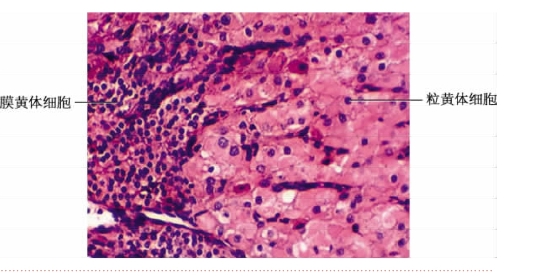

(3)黄体的形成和退化:排卵后,残留在卵巢内的卵泡壁塌陷形成一个暂存的内分泌细胞团,新鲜时呈黄色,故称黄体(图9-2-8)。由颗粒层细胞分化而成的粒黄体细胞呈多边形,胞体大,染色浅。细胞数量较多,分泌大量孕激素,主要为孕酮。来源于内膜细胞的膜黄体细胞体积较小,染色较深,数量较少。两种黄体细胞共同作用,产生一定量的雌激素。

图9-2-8 黄体局部光镜图

黄体的发育与排出的次级卵母细胞是否受精密切相关。若卵未受精,黄体维持两周即退化,称月经黄体。黄体细胞退化,由致密结缔组织瘢痕替代,形成白体。如果卵受精,在胎盘分泌的绒毛膜促性腺激素的作用下,黄体继续发育增大,直径可达5 cm,称妊娠黄体。它可维持6个月,以后也退化为白体,白体逐渐被巨噬细胞吸收。